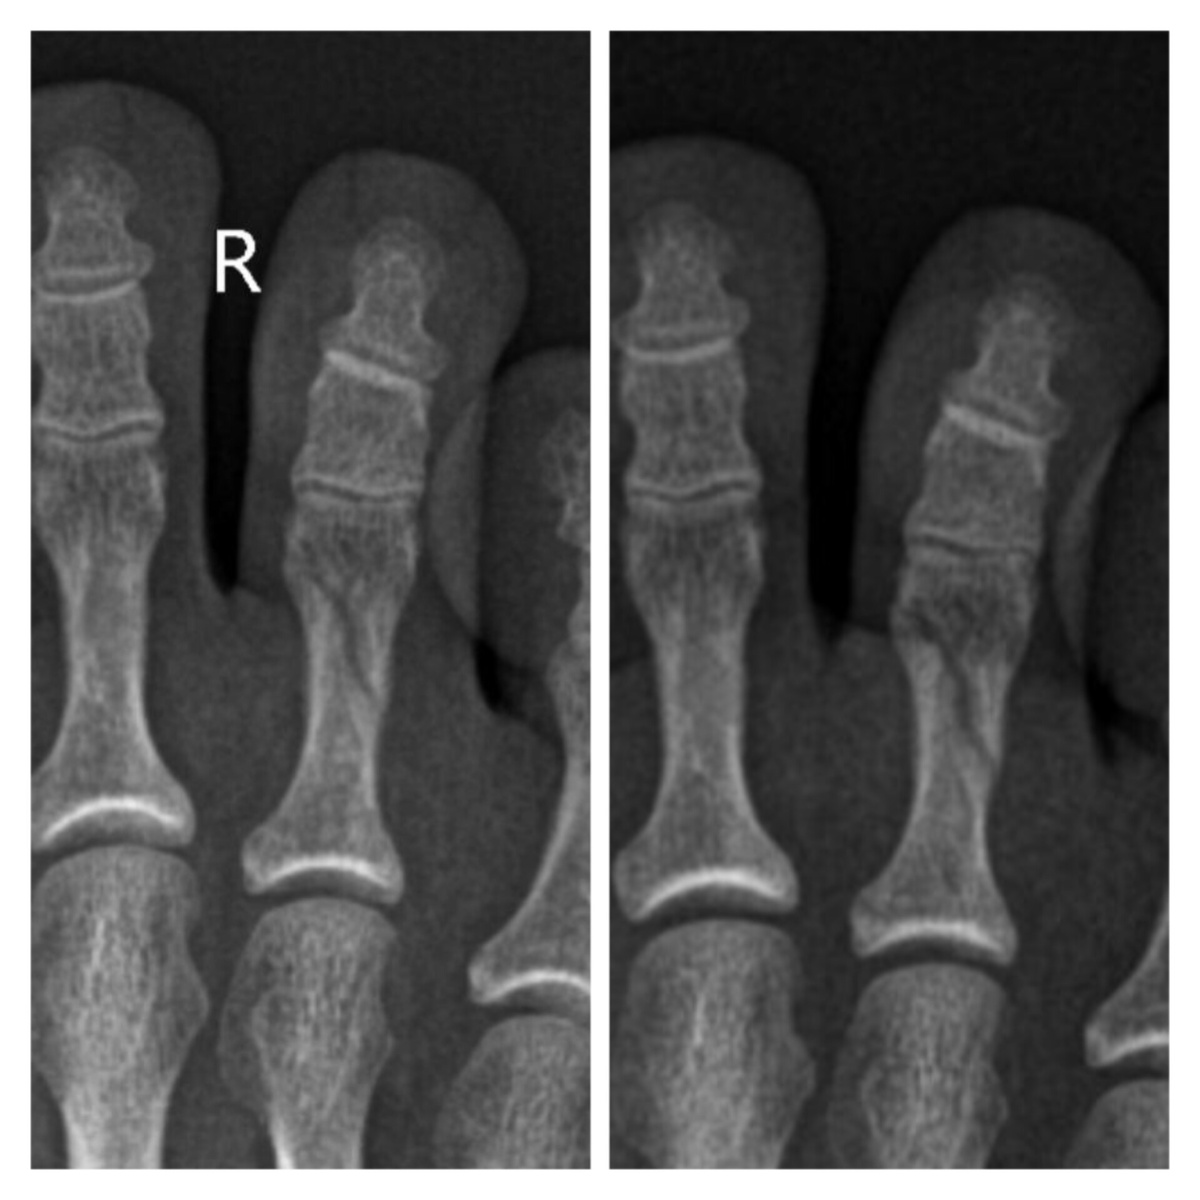

Вот так выглядит полный косой перелом пальца

За месяц на рентгене почти никаких изменений. Хотя доктор с рентгенологом пытались поднять мне настроение, мол, да, перелом еще не сросся, но на снимке есть положительная динамика.